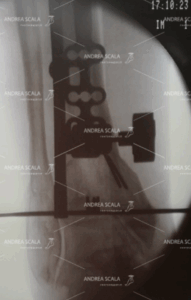

La RXgrafia intra operatoria mostra la visione anteriore dell’apparato di misurazione esterno all’osso della gamba. Il grande apparato deve essere allineato all’asse longitudinale della gamba. La sottile linea metallica assicura che la protesi avrà un andamento parallelo al suolo e che sarà perpendicolare all’asse longitudinale della gamba.

La RXgrafia intra operatoria mostra la visione laterale di un congegno applicato all’asta di allineamento esterna della tibia. Si tratta di un blocchetto di plastica trasparente all’interno del quale sono state montati dei reperi metallici, visibili alla RXgrafia intra operatoria. La genialità di questo congegno è che mostra in anticipo come sarà la protesi di caviglia:

– la linea continua orizzontale più lunga rappresenta il taglio della tibia;

– la linea continua orizzontale più breve localizza la articolazione della protesi (polietilene);

– i 4 puntini rappresentano il livello del taglio dell’astragalo.

Da questa FIGURA si capisce in maniera intuitiva che l’osso del paziente viene tagliato in maniera minima. Soprattutto l’astragalo.